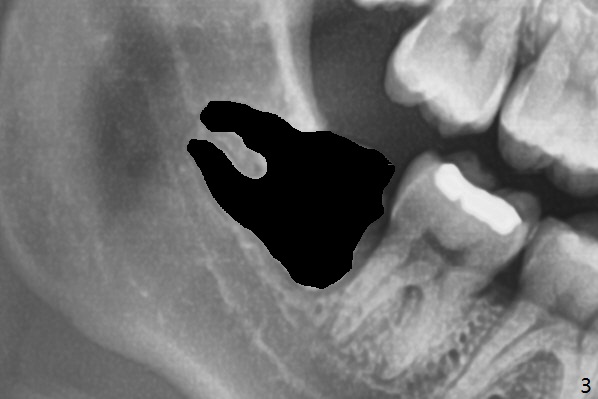

When the tooth #17 is extracted (Fig.9; 23 years old), collagen plug is inserted into the root portion of the sockets (Fig.10: 1 (white outline)), Vanilla graft is placed against the distal surface of #18 (2 (red outline)) and Osteogen plug (3 (green outline)) is placed coronally (3 steps). There is no bony defect associated with the distal surface of the tooth #18 immediate postop (Fig.11 (red dashed line: bone graft)). The wound heals in 2 weeks.